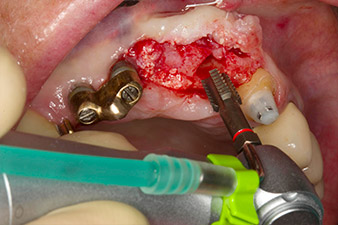

Механично поставяне на имплант

Фиг. 4: Механично поставяне на имплант с обратен наконечник WS-75 L и съотношение 20:1 (програма P5).

С цел да се компенсира периодонталната загуба на кост и да се постигне естетически добър резултат, имплантирането е комбинирано с водена костна регенерация (GBR) с ксеногенен заместващ материал и колагенова мембрана (Фиг. 5 и 6).